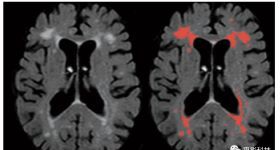

伴隨年齡增長的定向腦功能障礙會對認知和智力能力產生嚴重影響,相當一部分老年人經歷嚴重的認知下降,對功能性...